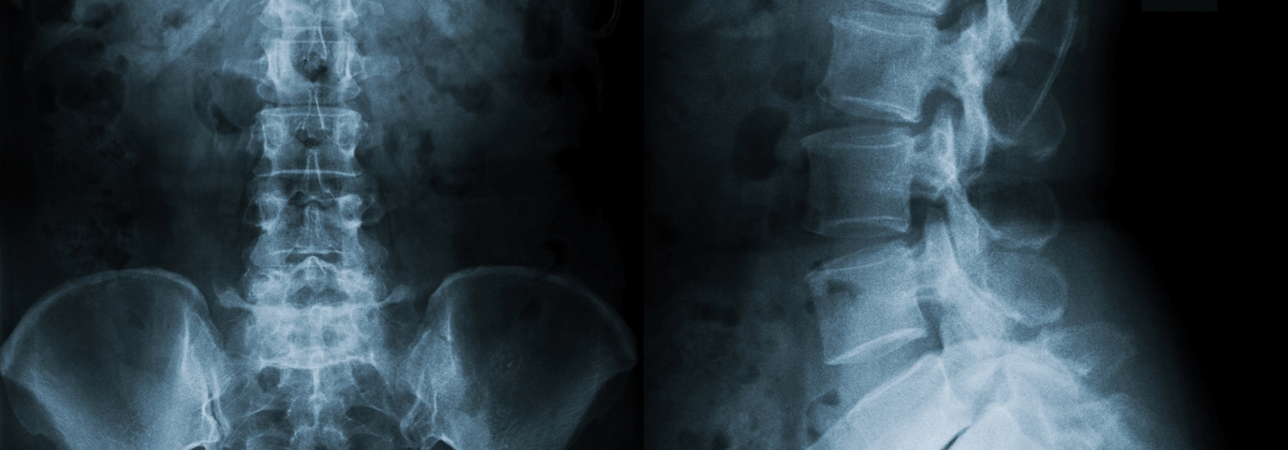

«Si tratta di una struttura altamente qualificata operante attraverso una sede principale all’interno del prestigioso complesso Ambrosart a Manno e una sede secondaria a Muralto- Locarno, all’interno di Tertianum Residenza Al Parco. Il Centro riunisce diversi specialisti che afferiscono alla colonna vertebrale, lavorando in sinergia per una presa in carico all’avanguardia e multidisciplinare, quindi completa, di pazienti con dolori correlati a disturbi della colonna vertebrale, offrendo loro l’opportunità di disporre di tutte le visite mediche, gli accertamenti, gli esami diagnostici e i trattamenti necessari. In sintesi, il Centro dispone di tutte le competenze grazie alle quali l’anamnesi clinica è accompagnata da un complemento diagnostico rapido ed una proposta terapeutica individualizzata alla ricerca del migliore percorso terapeutico e riabilitativo».